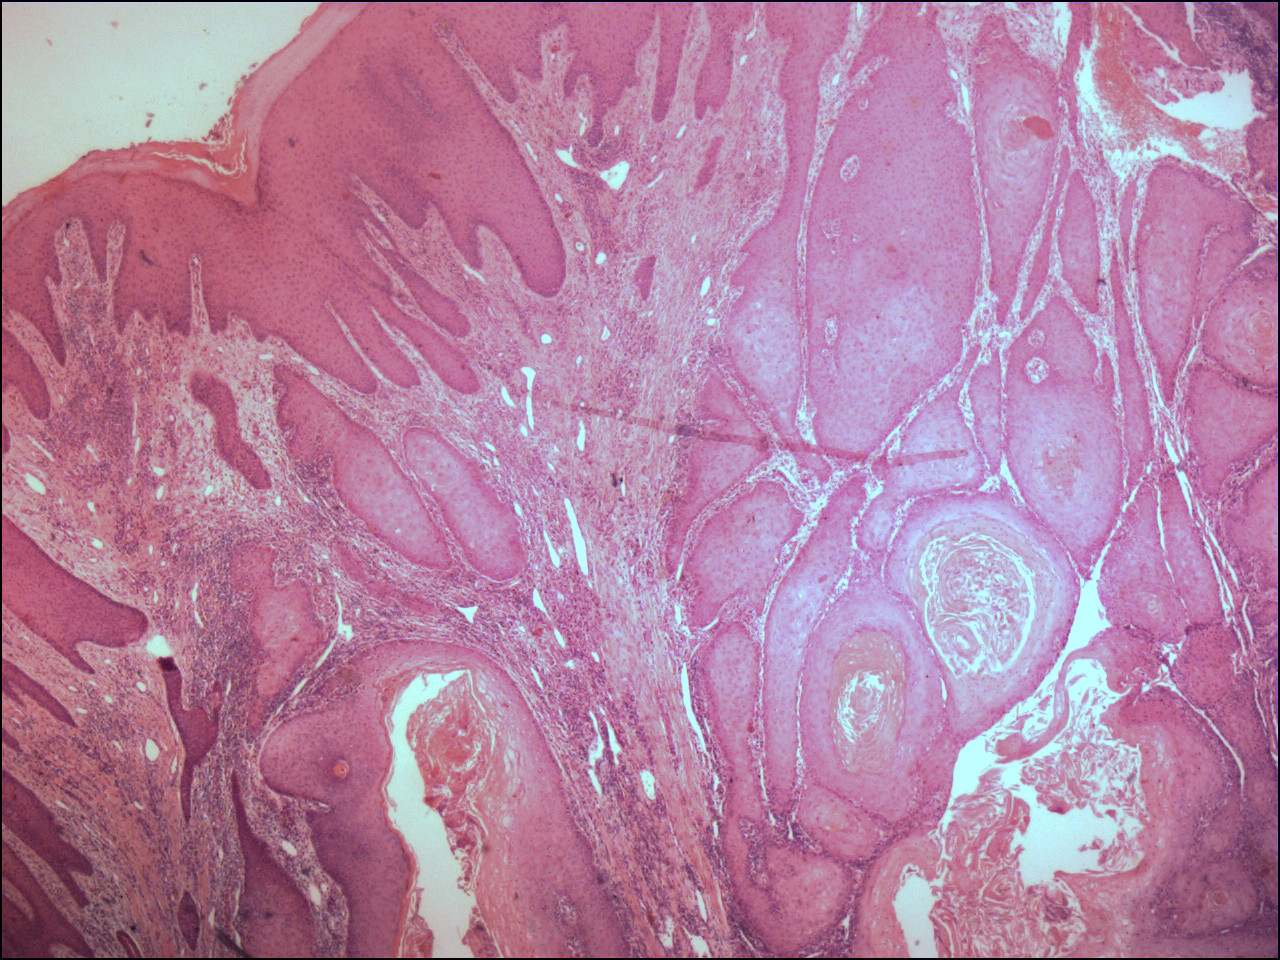

![Verruceus carcinoom (PA) (click on photo to enlarge) [source: www.huidziekten.nl] Verruceus carcinoom (PA)](../../../images/verruceus-carcinoom-3z.jpg) |

![Verruceus carcinoom (PA) (click on photo to enlarge) [source: www.huidziekten.nl] Verruceus carcinoom (PA)](../../../images/verruceus-carcinoom-4z.jpg) |

verruceus carcinoom |